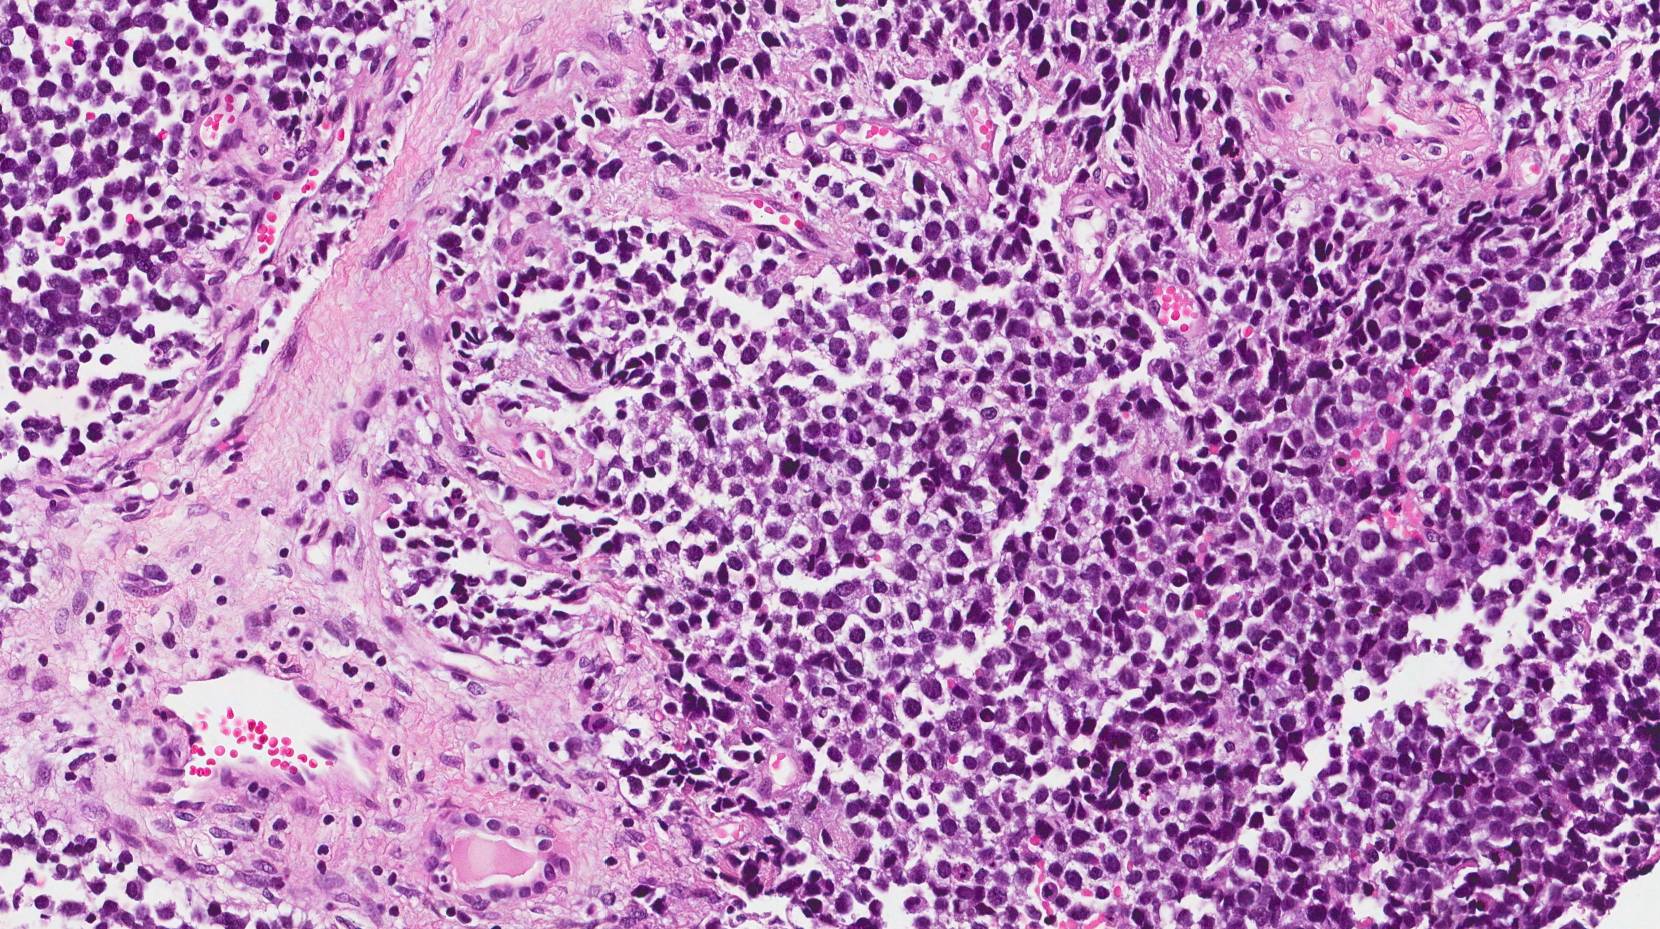

Biopsy: A definitive diagnosis of RMS is made by removing a sample of the tumour tissue and examining it under a microscope. This can be done through needle aspiration, core biopsy, or surgical biopsy, depending on the tumour's location.

Immunohistochemistry: Special staining techniques are used to identify rhabdomyoblasts (cells that are characteristic of RMS) and other markers such as Myogenin, MyoD1, and Desmin. This helps confirm the diagnosis and differentiate RMS from other types of soft tissue sarcomas.